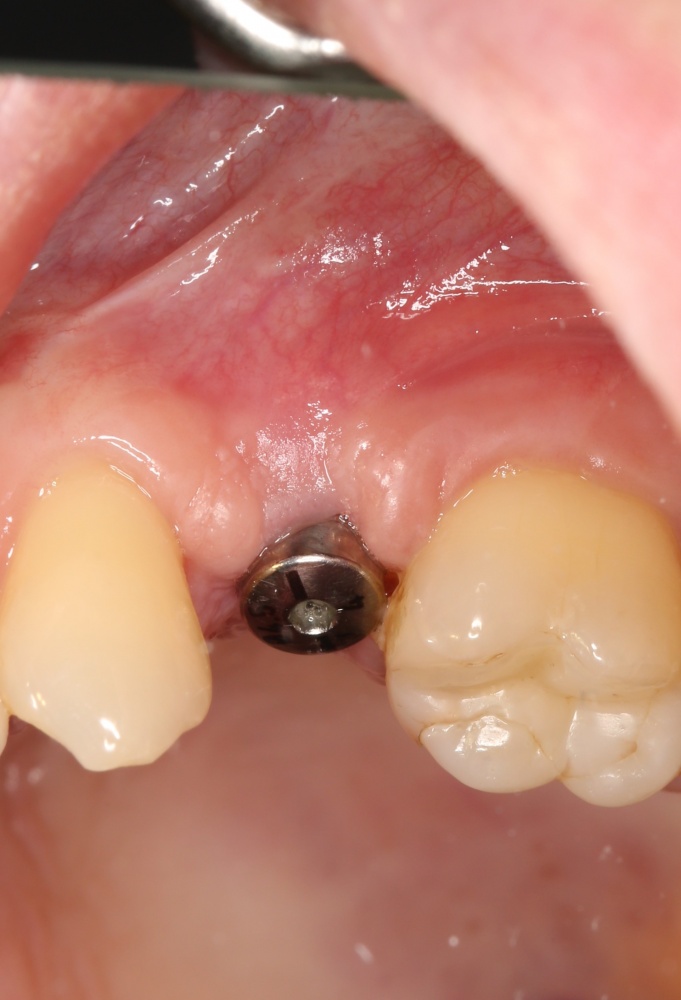

Простой. Надежный. Дешевый. Способ остеопластики.